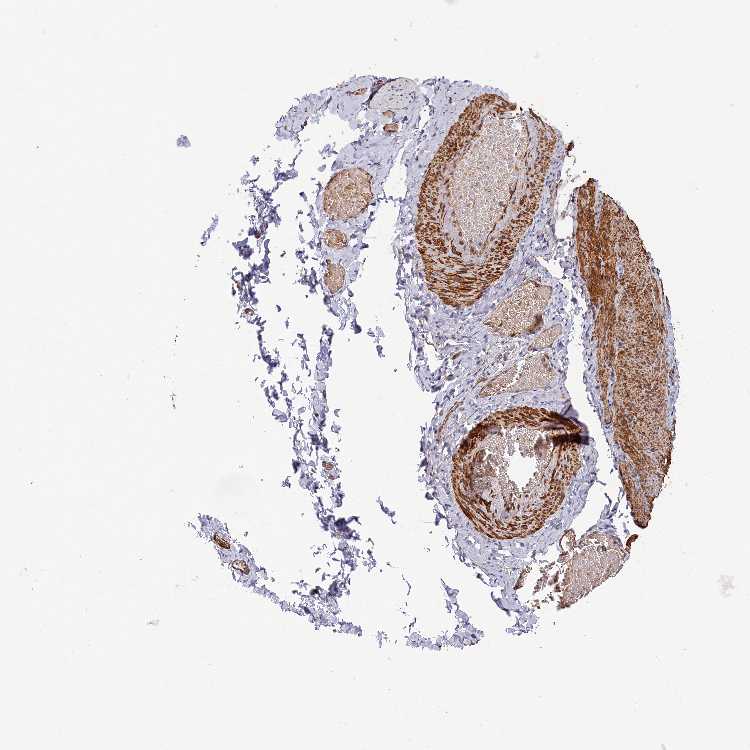

SOFT TISSUE 2 - Antibody stainingi

Antibody staining in the annotated cell types in the current human tissue is reported as not detected, low, medium, or high, based on conventional immunohistochemistry profiling in selected tissues. This score is based on the combination of the staining intensity and fraction of stained cells.

Each image is clickable and will lead to virtual microscopy that enables deeper exploration of all samples and also displays staining intensity scores, fraction scores and subcellular localization as well as patient and tissue information for each sample.

Antibody HPA041766Antibody HPA048639

Chondrocytes MediumNot detected

Fibroblasts LowNot detected

Peripheral nerve Low-